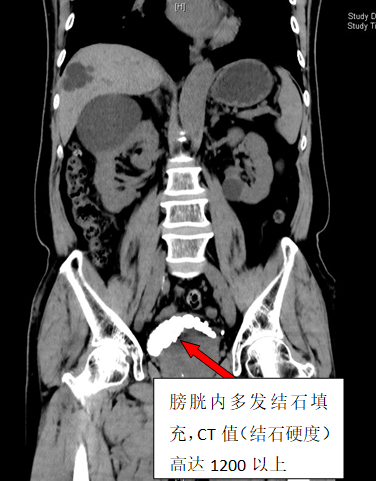

79岁李雄(化名)四年来一直被反复的尿频、血尿、下腹胀痛不适所困扰。在家人多次劝说下,他来到香港马会app 泌尿外科二区就诊。CT检查结果显示李大爷膀胱内布满了30余枚结石,犹如月球表面的环形山,其中最大的那颗直径达3厘米,几乎占据了膀胱1/3的空间。

手术当天,泌尿外科二区团队凭借精湛的技术和丰富的经验,为李大爷实施了经尿道钬激光碎石手术。整个碎石过程历时2小时,医护人员精准操作,共发出13800次激光脉冲,将30枚结石打碎取出。术后CT三维重建显示,李大爷的膀胱腔隙内结石已清除干净。